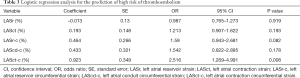

Logistic regression analysis

Logistic regression analysis of patients with AF revealed that LASct-c was independently associated with a high risk of thromboembolism [odds ratio (OR): 2.52, CI: 1.27 to 4.99, P=0.008; Table 3 and Figure 3]. In patients with NVAF, LASct-c was found to be able to distinguish between high and low risk of thromboembolism, and the area under the curve (AUC) was 0.95 (P<0.001; Figure 4). The most approximate Youden index was 0.85, while the corresponding value of LASct-c was –4.5%. At this point, sensitivity and specificity were 0.872 and 0.978, respectively.

Full table